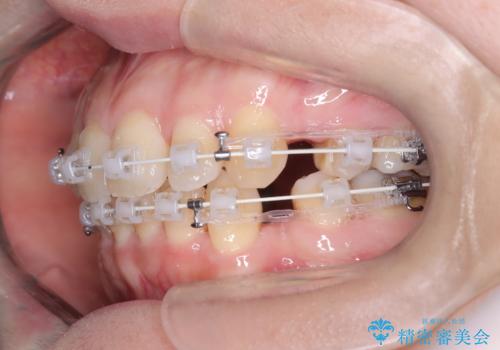

- 矯正装置

- ワイヤー(審美装置)

- 治療計画

- 「歯のデコボコと前歯が出ているせいで口が閉じにくい」を主訴に来院された患者様です。

上下左右の4番(第一小臼歯)を抜歯をし審美ワイヤー装置で治療を行いました。

抜歯矯正により歯列のデコボコ(叢生)が改善し、前歯の突出も解消されたことで口元が下がり、すっきりとした印象となりました。